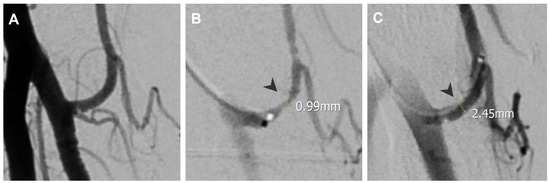

| Lateral epicondylitis | Radial recurrent artery | 1.00 | 2.5 |